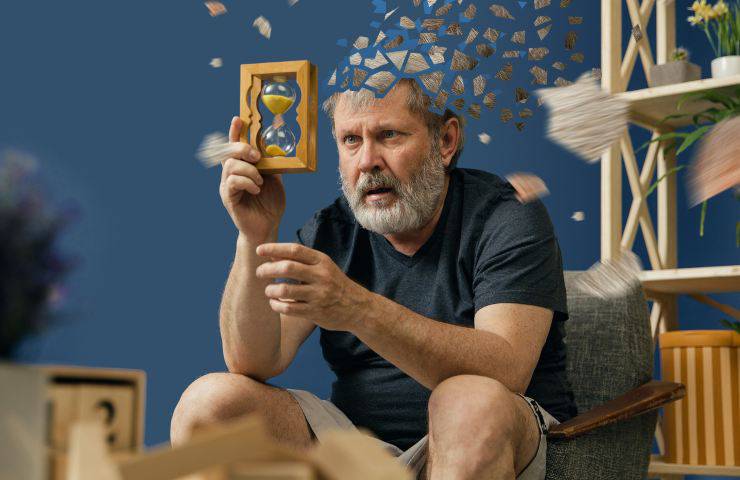

Lo studio di cui stiamo disquisendo è stato condotto dalla National University di Singapore ed è stato pubblicato sul Journal of Alzheimer’s Disease.

Per tale ricerca, sono stati seguiti per ben 6 anni oltre 600 anziani ed è stato riscontrato che il consumo di mezzo piatto di funghi a settimana equivale ad una diminuzione del 50% per quanto riguarda l’Alzheimer.

La porzione designata per ricevere tale scopo è di 300 grammi a settimana. Grazie a questi infatti si potrà rinviare l’invecchiamento del cervello e il declino cognitivo.